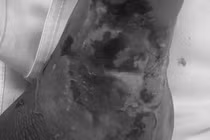

Trẻ đã hồi phục sau hồi sức tích cực - Ảnh BVCC